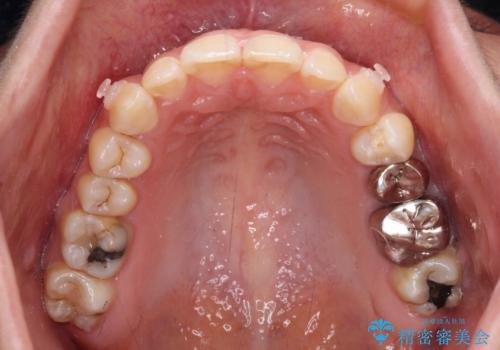

- 下顎の前歯が隠れていることと、デコボコを気にして来院された患者様です。

目立ちにくい装置を希望されていたため、ワイヤー装置とインビザラインを提案したところ、インビザラインを希望されました。

銀歯やムシ歯処置の必要な歯が奥歯にあり気になっていたので、矯正治療の途中でセラミッククラウンへ変更し、その後歯列を仕上げていくこととしました。